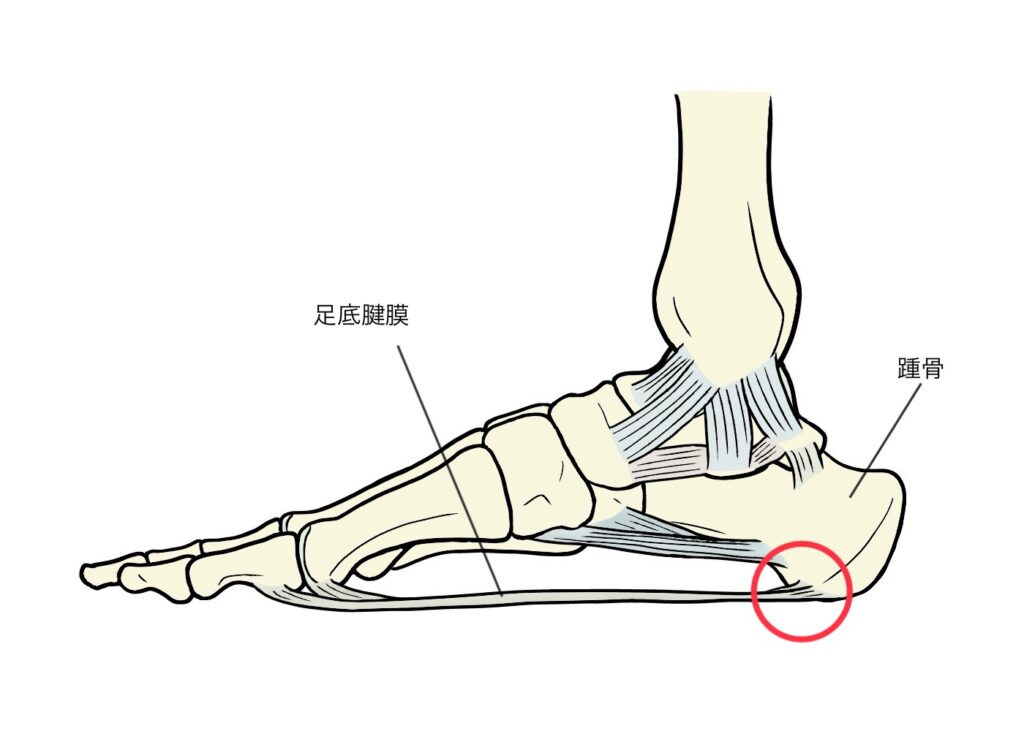

足底腱膜炎とは、足底腱膜と呼ばれる足の裏に存在する腱膜が炎症を起こした状態のことです。

踵骨棘とは

踵骨棘は、かかとの骨(踵骨)から余分なとがった骨が増殖したものです。足底に伸びている結合組織である足底腱膜により、踵骨に過度な張力がかかることで骨棘ができることがあります。踵骨棘が、必ずしも症状を引き起こすわけではありませんが多くの場合、強い痛みを引き起こします。症状が生じる場合でも、ほとんどは手術をしなくても治療できます。